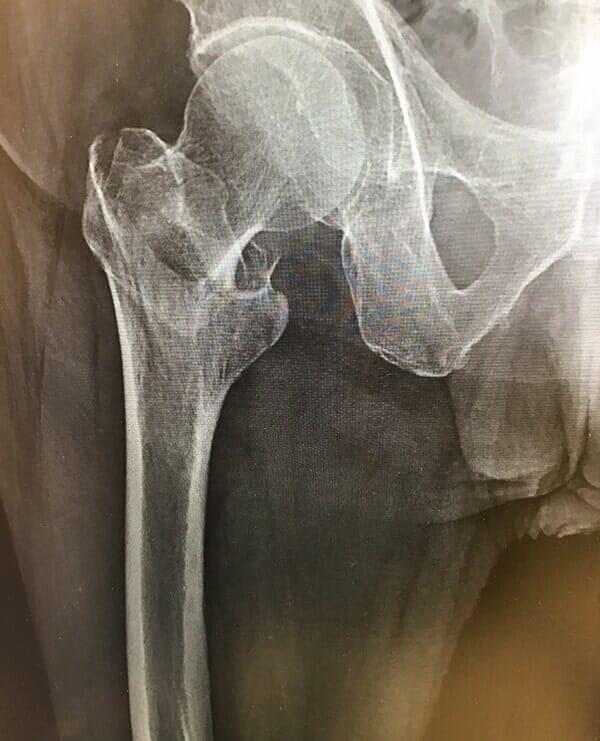

En esta área de la medicina, el Dr. Gerardo Guerrero Yeo se caracteriza por buscar soluciones a enfermedades médicas que afectan tejidos y articulaciones que ocasionan dolor, limitación o rigidez del movimiento locomotor.